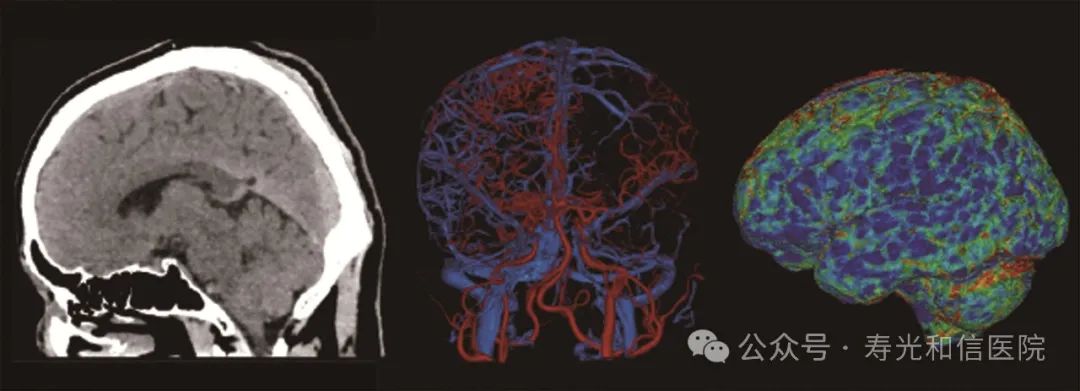

4D 一站式卒中检查

联影640层CT采用宽体采集,一次检查即可获得全脑平扫图像、动静脉造影图像和灌注图像,不仅可应用于急诊缺血性脑卒中的影像评估,还可助力脑血管畸形、脑动脉瘤等其他脑血管病的结构和功能评估。